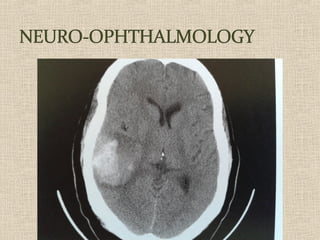

VISUAL EVOKED

POTENTIAL - VEP

 The visually evoked potential (VEP)

measures the electrical response of

the brain's primary visual cortex to

a visual stimulus.

NEURO-OPHTH DISORDERS

OPTIC PATHWAY DISORDERS

EXCLUDING CRITERIA

MEDICAL LEGAL

OTHERS